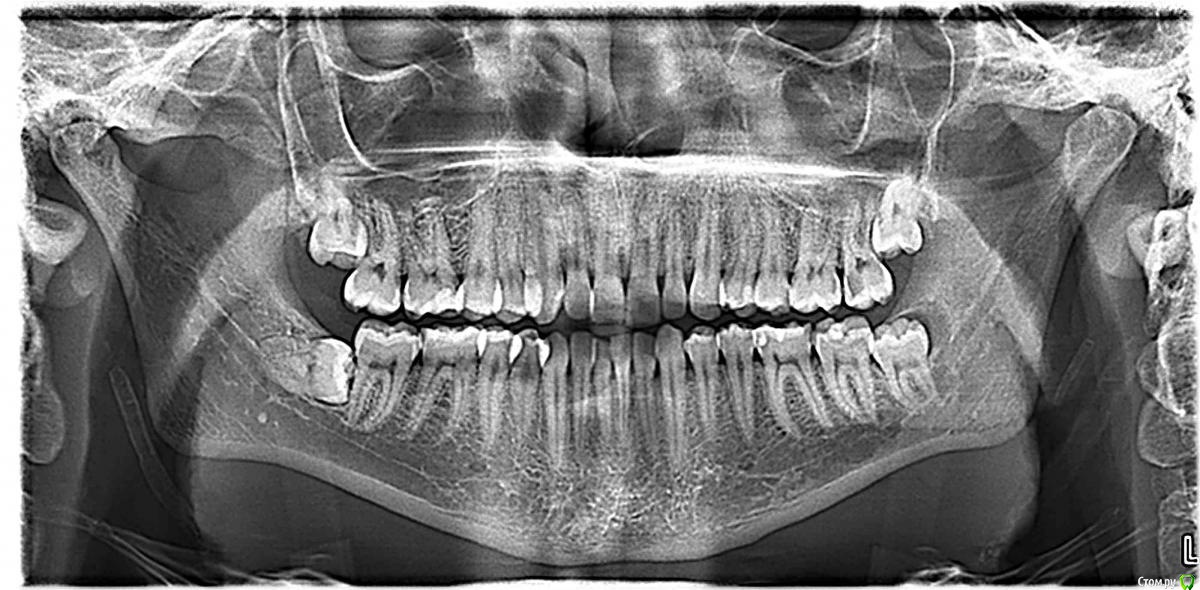

lubaka Опубликовано 23 июня, 2016 Поделиться Опубликовано 23 июня, 2016 Здравствуйте! У моего мужа над нижним левым зубом мудрости киста. Один врач сказал, что нужно удалять в больнице, и операция сложная. Другой говорит, что вырвет за полчаса. Подскажите, кому верить и что делать. Спасибо! Ссылка на комментарий

St. Опубликовано 23 июня, 2016 Поделиться Опубликовано 23 июня, 2016 Удалять, и все остальные зубы мудрости тоже. На нижних больше беспокоит близость корней к нерву в нижней челюсти. С тем ореолом что вы назвали кистой проблем быть не должно. Нормальный доктор в частной вполне справится, попробуйте поискать на форуме. 5 Ссылка на комментарий